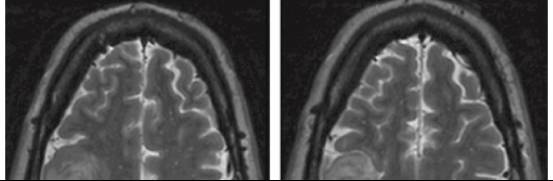

图5. 皮层低级别胶质瘤可导致其上覆盖皮质的形态学发生变化(左图)或无变化(右图)。左图显示右额叶运动前区皮层的扩大和矢状窦旁静脉向后移位。右图显示右额叶后部的肿瘤(绿色丝线标记边界)引起很小的皮层形态改变。